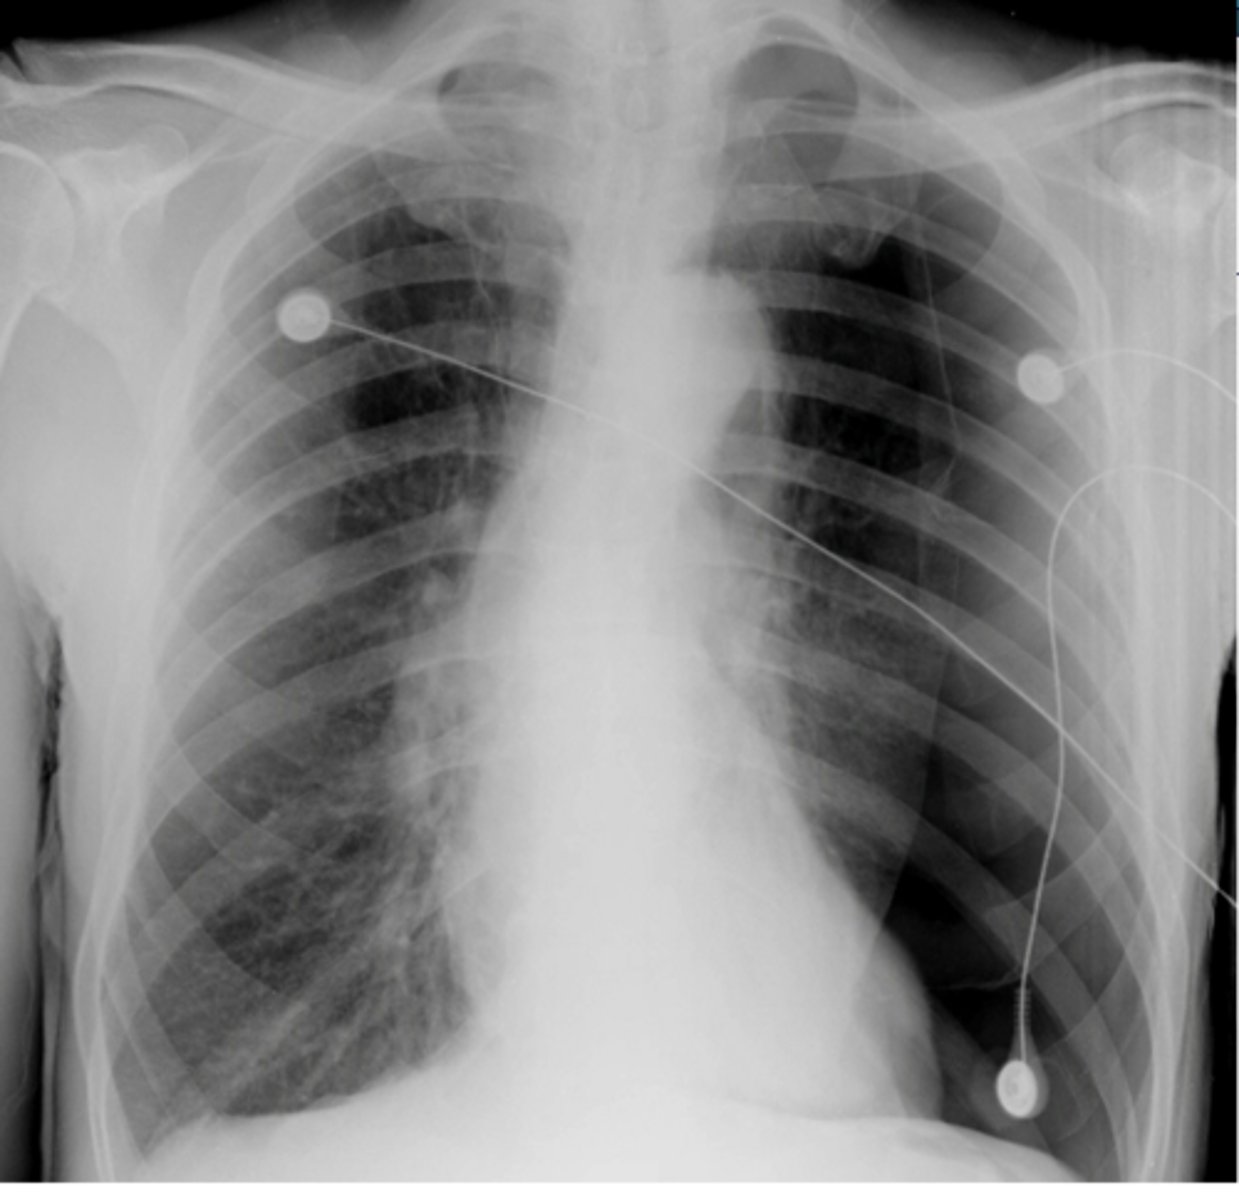

oAir in the pleural space (pneumothorax) is usually seen in the apices if the patient is upright.

Seen as an area of no vascularity and a thin white line representing the visceral pleura

**air has no density (so air will show up as darker)

What will pneumothorax look like on imaging? What area of the lungs does pneumothorax affect?

L sided moderate pneumothorax

Dx

<p>Dx</p>

-mediastinal shift

-less density (darker)

-sharp line if non-tension pneumothorax

3 key findings for pneumothorax